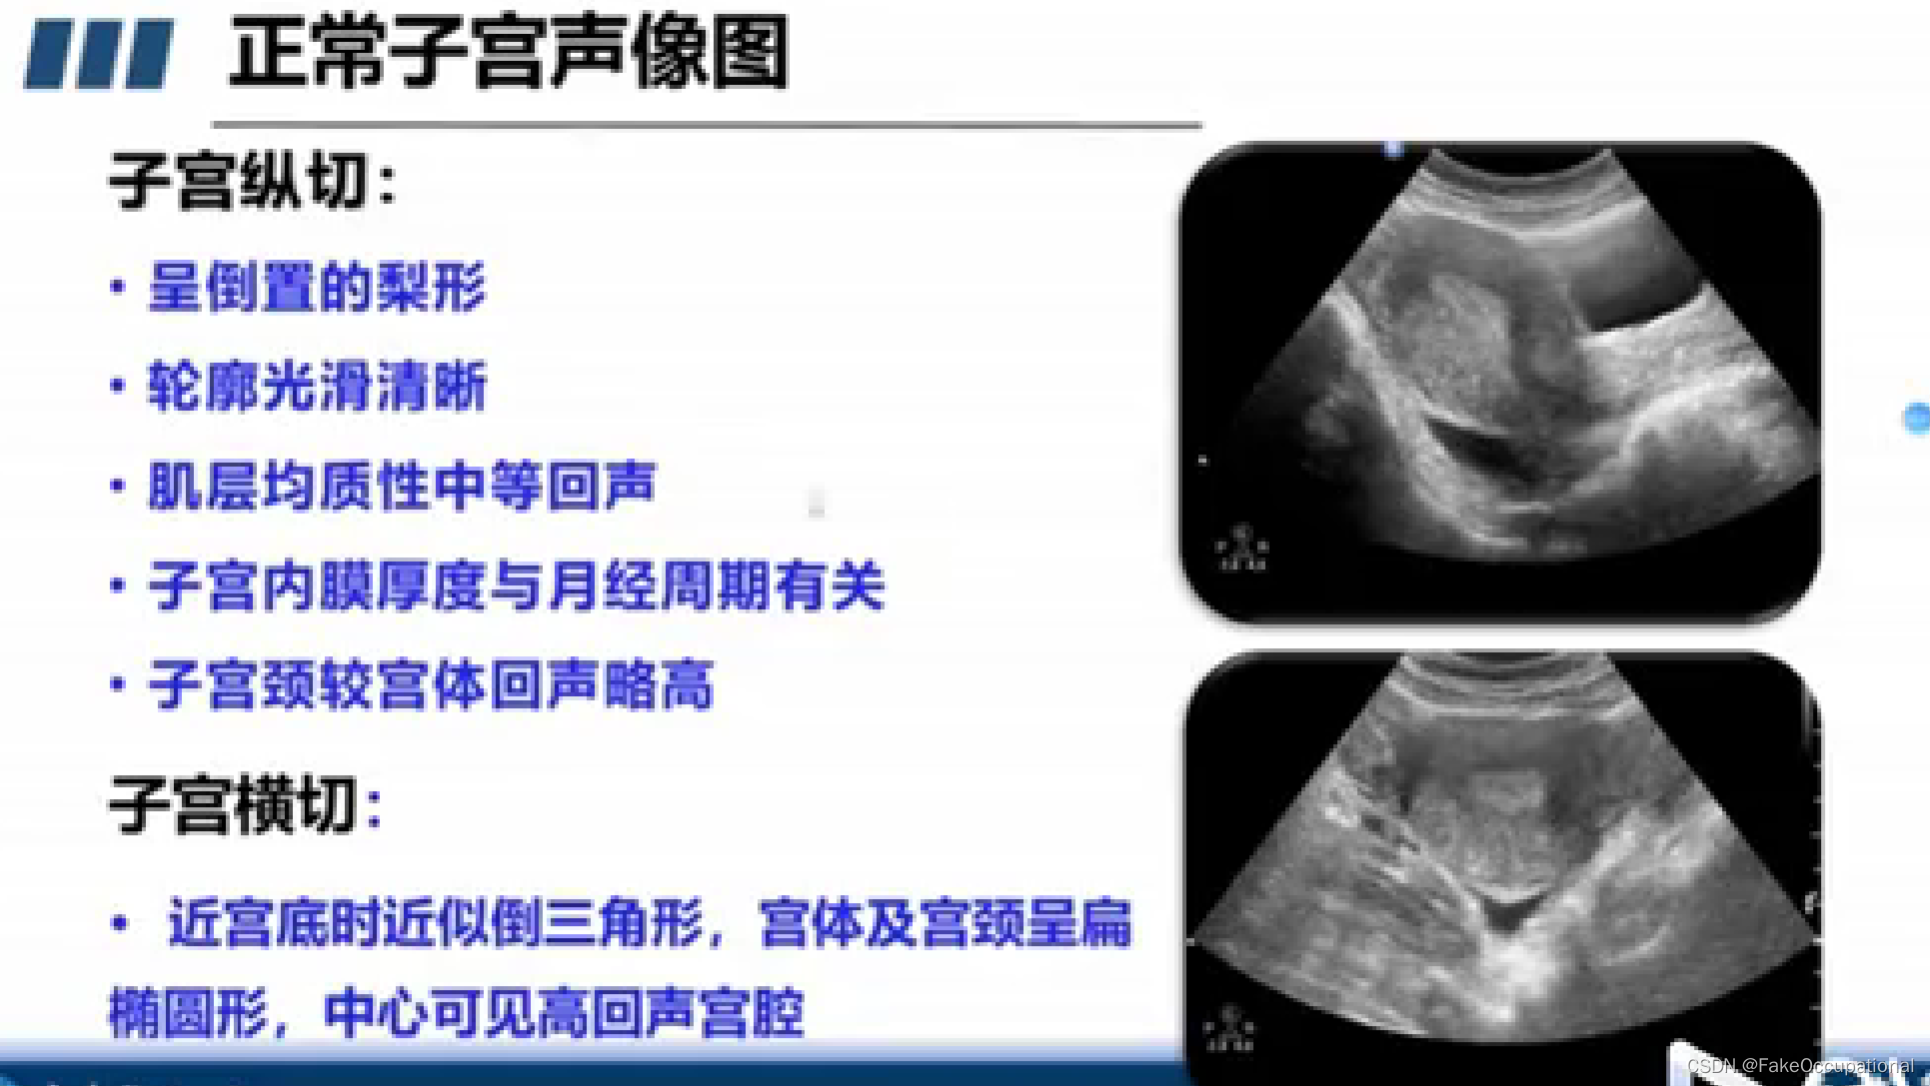

正常子宫和卵巢声像图